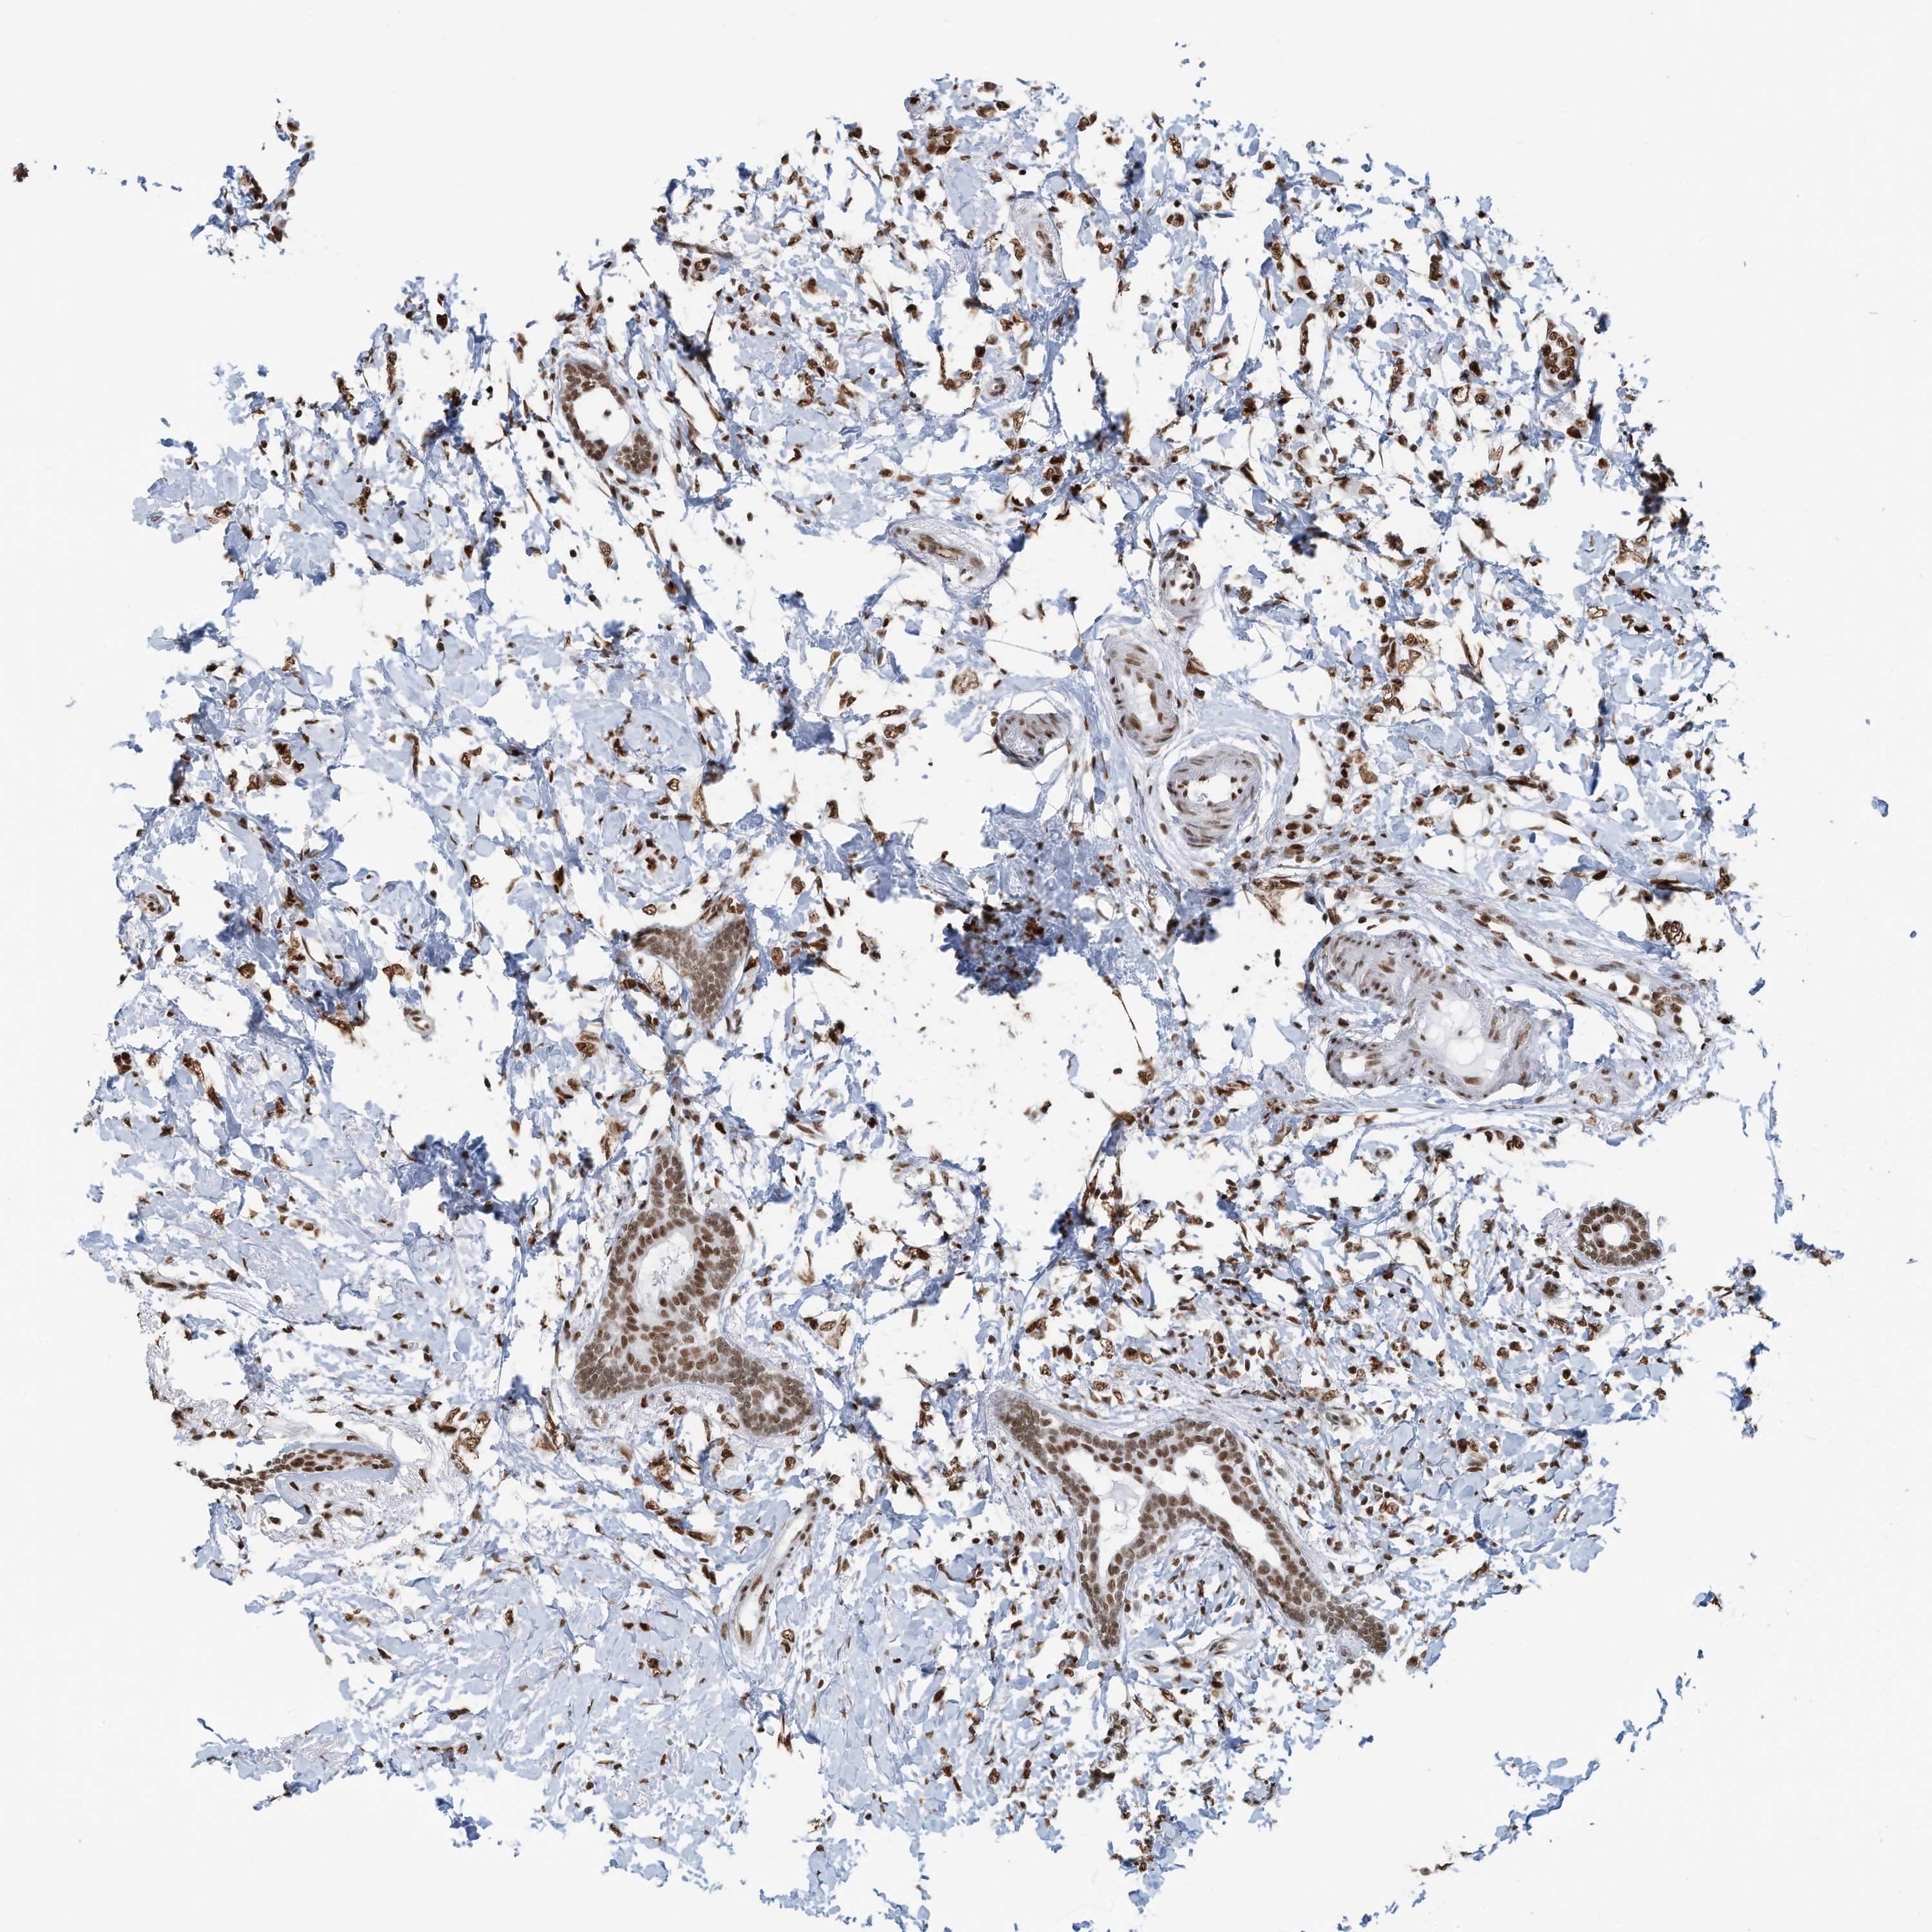

CANCER BREAST CANCER Show tissue menu

BRCA TCGA BRCA VALIDATION PROTEIN EXPRESSION